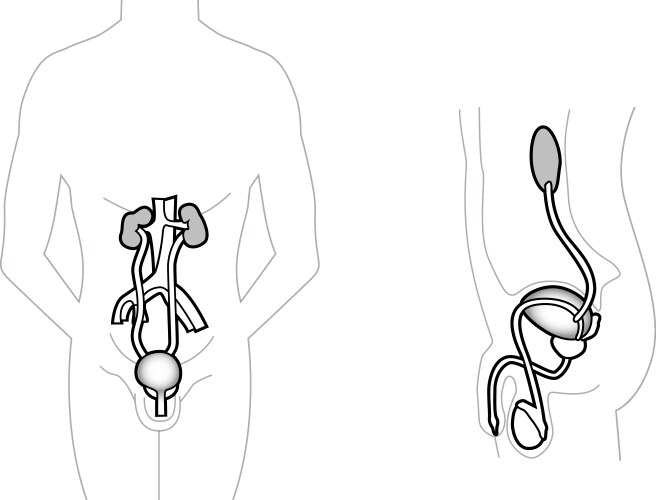

- Anatomy

- Reproductive

- Anatomical

- Biological

- Biology

- Body

- Physiology

- Urology